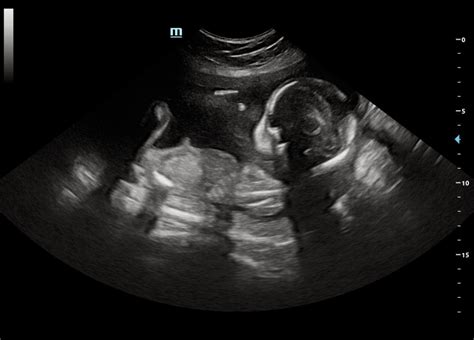

Alright, folks, let’s kick things off by really understanding what this 20-week anatomy scan actually is. This isn’t just any old ultrasound; it’s a major milestone in your pregnancy journey, typically performed between weeks 18 and 22, with week 20 being the sweet spot for optimal viewing. Think of it as a comprehensive, head-to-toe check-up for your little one, all while they’re still cozy in your womb. During this appointment, a specially trained sonographer or doctor will use high-frequency sound waves to create detailed images of your baby’s internal organs and external structures. This isn’t an X-ray, so it’s completely safe for both you and your baby. The primary goal here is to carefully examine your baby’s anatomy to ensure everything is developing as expected. They’ll be looking at everything from the shape of their skull and the structure of their brain, to their tiny beating heart and developing lungs. They’ll also check out their kidneys, bladder, stomach, spine, and even their cute little fingers and toes! Beyond organ development, the scan assesses the baby’s growth, measuring their head circumference, abdominal circumference, and femur length to ensure they’re growing appropriately for their gestational age. They’ll also check the amount of amniotic fluid surrounding the baby, as both too much or too little can sometimes indicate an issue, and they’ll examine the placenta’s position, which is crucial for nutrient delivery. This incredible technology allows us to gain invaluable insights into your baby’s well-being before they even arrive. For many parents, this is also the exciting moment where you might find out the gender of your baby, if you choose to know! But beyond the fun stuff, it’s a critical diagnostic tool. It’s a long appointment, sometimes taking 30 minutes to an hour or even more, because the sonographer needs to be meticulous, ensuring they capture all the necessary views. Patience is key, as your baby might not always cooperate, requiring you to shift positions or even take a little walk to encourage them to move into the best viewing angle. Ultimately, this scan provides crucial information that helps your healthcare team monitor your baby’s health and development, allowing for early detection and, if necessary, planning for any specific care your baby might need after birth. It’s a truly amazing blend of medical science and a deeply personal experience, offering a reassuring glimpse into the miracle growing inside you.